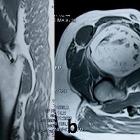

Osteolipomas are usually in the suprasellar and interpeduncular cistern, close to the pituitary infundibulum, inferior surface of the hypothalamus, mammillary bodies and tuber cinereum .

Central fat signal that attenuates on fat-saturated sequences is surrounded by calcification which results in low signal on most sequences and blooming on T2*/SWI sequences .